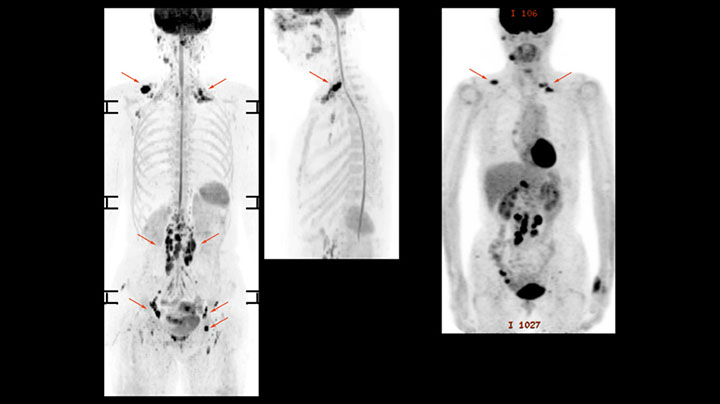

Whole body diffusion

A 61-year-old female with a malignant lymphoma underwent an MRI exam with whole body diffusion weighted imaging (DWIBS) as well as PET. On the images shown, the resolution of DWIBS is better than PET, which allows visualization of the small pelvic lesions and almost no distortion is seen in the neck area.